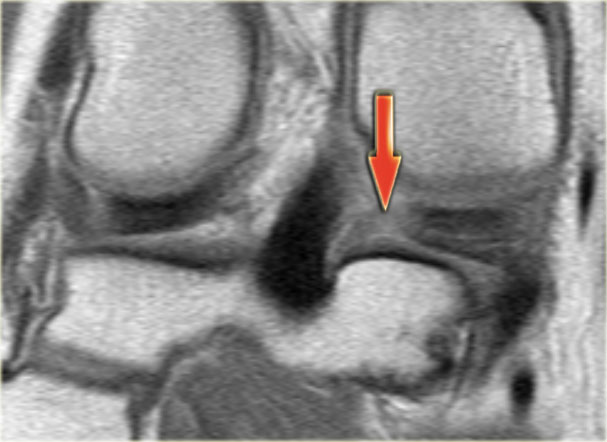

Bên trái là một trường hợp sụn chêm lật khác.

Lần này ở phía trong (medial).

Một phần sừng trước bị lật ra phía sau.

Chỉ một phần nhỏ của sừng trước được nhìn thấy ở phía trước.

Hầu hết các trường hợp sụn chêm lật xảy ra ở phía ngoài (lateral).

Dây chằng chéo trước (ACL) ngăn mảnh sụn chêm di chuyển hoàn toàn vào hố gian lồi cầu.

Trên hình ảnh mặt phẳng coronal, trước tiên sẽ thấy sừng trước to và phồng lên.

Ở phía sau sẽ thấy sừng sau rất nhỏ.